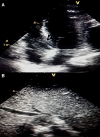

Case summary: Thirty-four-year-old woman with the unremarkable medical history presented with epigastric pain and dyspnoea. Electrocardiogram showed ST-segment elevation in the inferior limb leads. She underwent an emergency coronary angiogram, which showed a high thrombus burden in the distal right coronary artery. A subsequent echocardiogram demonstrated a 31 × 33 mm right atrial mass adhering to the inferior vena cava and abdominal computed tomography (CT) scan revealed a 113 × 85 mm necrotic mass in the left adrenal bed, with tumour thrombus extending proximally to the confluence of hepatic veins immediately inferior to the right atrium and distally to iliac vein bifurcation. Blood parameters, thrombophilia panel, vanillylmandelic acid, 5 hydroxy indole acetic acid, and homovanillic acid levels were normal. Tissue sampling confirmed the diagnosis of PHEOs. The surgical procedure was not planned due to the presence of metastatic foci on imaging, including positron emission tomography (PET)-CT. Anticoagulation with rivaroxaban and treatment with 177Lu-DOTATATE-based peptide receptor radionuclide therapy (PRRT) was initiated.